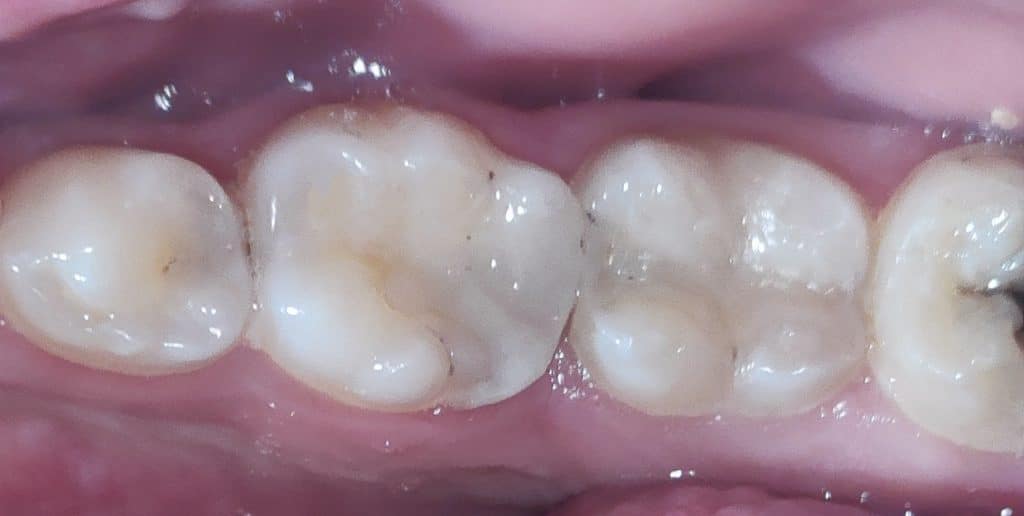

4-I tend to restore tooth no,37 first then tooth no,36 using sectional and saddle matrix system form TorVM

5- After finishing anatomy carving and shaping , I gone to finish restoration with yellow coded carbide flame and pre-polishing tips from Kenda

6- finally, polishing step using impreganted brush from ENA